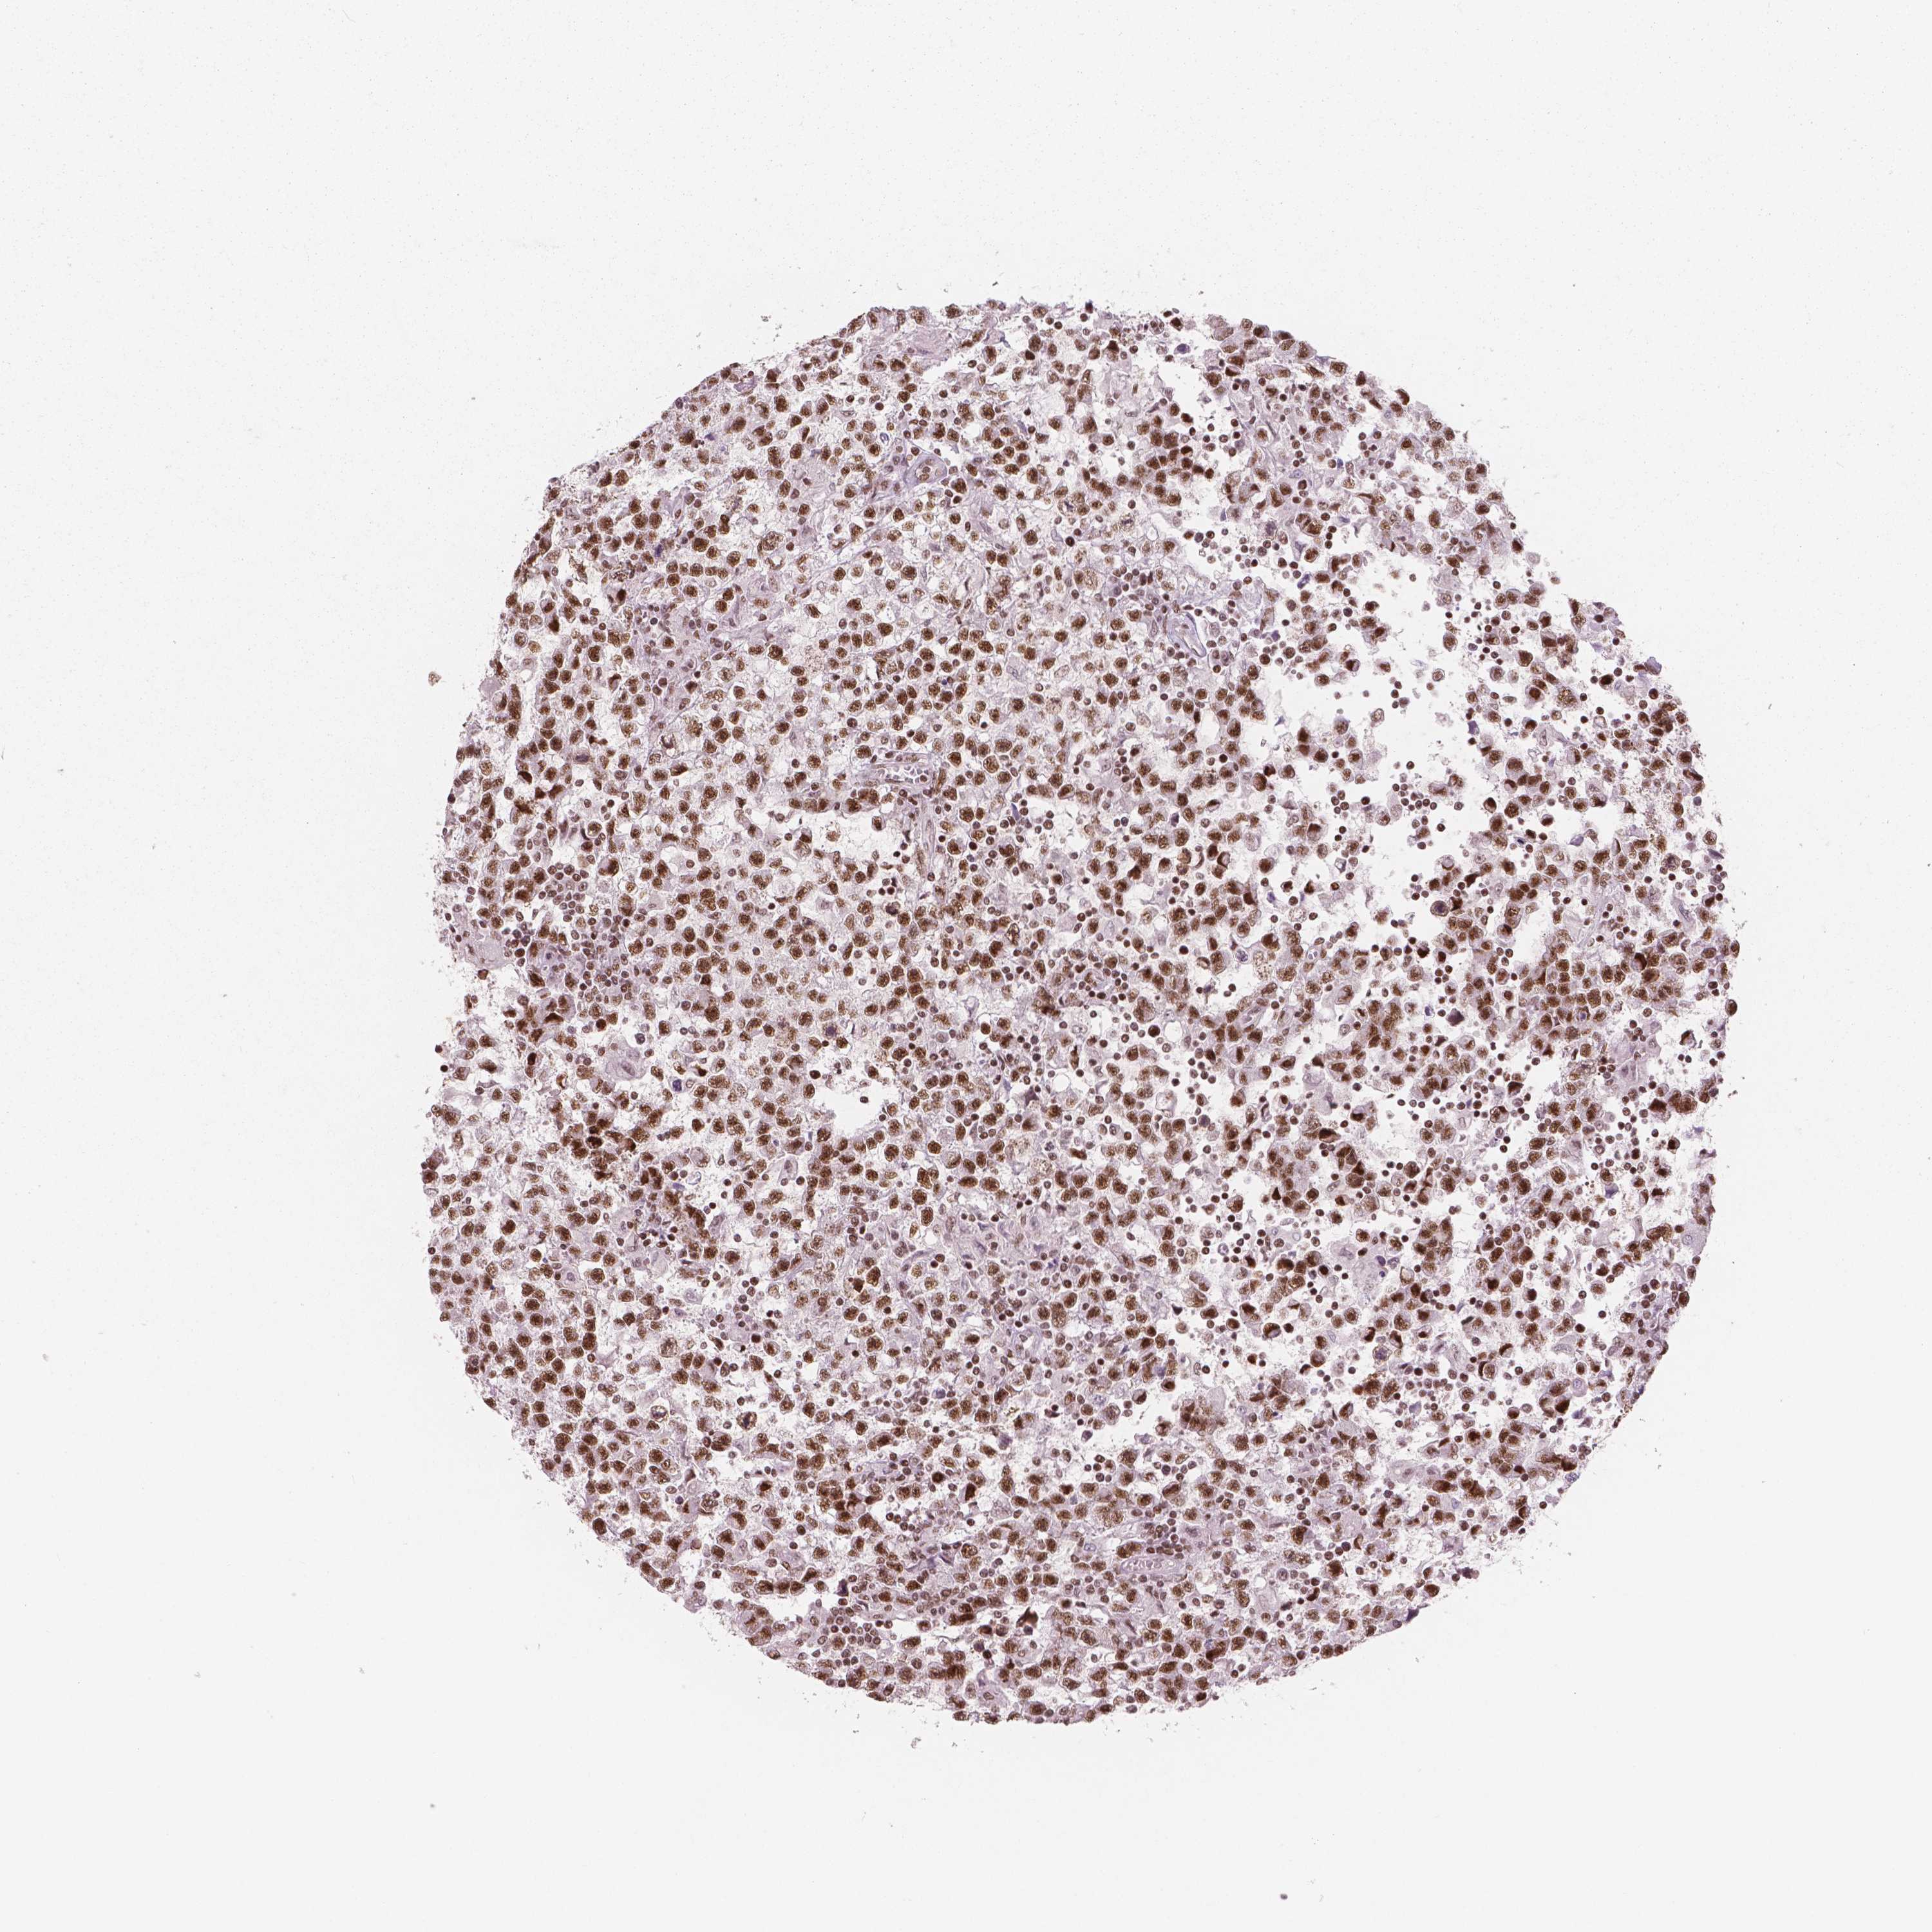

TESTIS CANCER - Protein expressioni

A mouse-over function shows sample information and annotation data. Click on an image to view it in a full screen mode. Samples can be filtered based on level of antibody staining by selecting one or several of the following categories: high, medium, low and not detected. The assay and annotation is described here.

Note that samples used for immunohistochemistry by the Human Protein Atlas do not correspond to samples in the TCGA dataset.

Antibody stainingi

Antibody staining in the annotated cell types in the current human tissue is reported as not detected, low, medium, or high, based on conventional immunohistochemistry profiling in selected tissues. This score is based on the combination of the staining intensity and fraction of stained cells.

Each image is clickable and will lead to virtual microscopy that enables deeper exploration of all samples and also displays staining intensity scores, fraction scores and subcellular localization as well as patient and tissue information for each sample.

Antibody HPA015055

Carcinoma, Embryonal, NOS

Seminoma, NOS